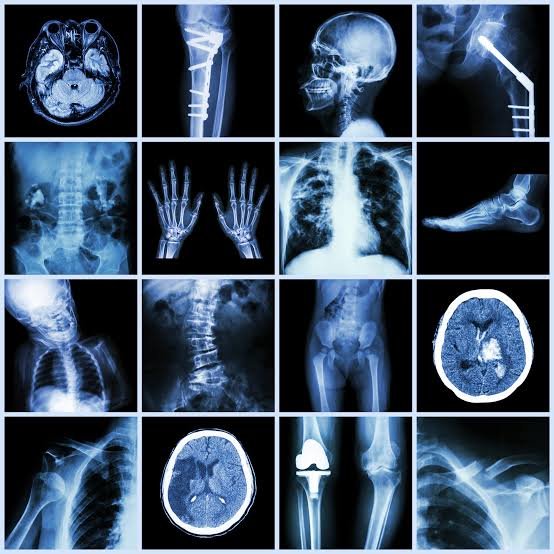

चिकित्सा के क्षेत्र में तकनीक ने क्रांति ला दी है, लेकिन अनावश्यक रेडियोलॉजिकल जांच जैसे एक्स-रे और सीटी स्कैन की बढ़ती प्रवृत्ति मरीजों के लिए खतरा बन रही है। शनिवार को राम मनोहर लोहिया अस्पताल में आयोजित न्यूरोलॉजिकल सर्जंस सोसाइटी ऑफ इंडिया के दो दिवसीय प्रशिक्षण कार्यक्रम में डॉ आरएस मित्तल ने यह बातें कही।

उन्होंने चेतावनी दी कि बार-बार रेडियोलॉजी जांच से होने वाला विकिरण जोखिम खासकर 20 वर्ष से कम उम्र के मरीजों में कैंसर का खतरा 10 प्रतिशत तक बढ़ा सकता है। इस कार्यक्रम में विभिन्न राज्यों में डॉक्टरी की पढ़ाई कर रहे छात्र शामिल थे, जिन्हें 15 से 40 साल के अनुभवी डॉक्टरों ने प्रशिक्षण दिया। इस प्रशिक्षण में छात्रों को मरीजों की जांच करना, बीमारी का पता लगाना, बीमारी में इलाज की जरूरतों को समझना, जरूरत न होने पर सर्जरी करने से बचना व एक अच्छा न्यूरो सर्जन बनने का प्रशिक्षण दिया गया।

सोसाइटी के संस्थापक अध्यक्ष और न्यूरो सर्जन प्रो. आरएस मित्तल ने कहा कि तकनीक पर अत्यधिक निर्भरता के कारण मैनुअल जांच की कला कमजोर पड़ रही है। उन्होंने कहा कि जब तक अत्यंत आवश्यक न हो, रेडियोलॉजी जांच से बचना चाहिए। मैनुअल परीक्षण को बढ़ावा देकर न केवल मरीजों के स्वास्थ्य की रक्षा की जा सकती है, बल्कि अनावश्यक खर्च और जोखिम भी कम किए जा सकते हैं। एनएसएसआई के पूर्व अध्यक्ष प्रो. एमके तिवारी ने बताया कि कृत्रिम बुद्धिमत्ता (एआई) के युग में भी मानवीय विशेषज्ञता की कोई बराबरी नहीं है। एआई हमें दिशा दिखा सकती है, लेकिन मरीज की स्थिति को समझकर सही जांच का चयन केवल प्रशिक्षित सर्जन ही कर सकते हैं।